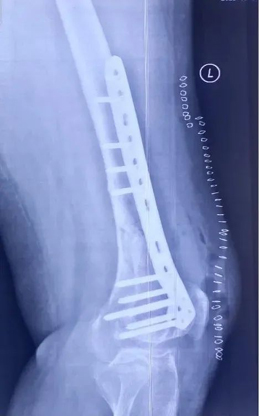

其次,定制化接骨板的形态设计是以患者的个人CT数据为参考,完全根据患者个人的解剖形态而打印制造,与患者股骨远端解剖形态完全一致,便于手术中骨折的复位固定; 另外接骨板钉孔设计参考了骨折端的解剖形态和生物力学特点,骨折端的接骨板形态得到了强化设计,并同时计算了手术中所需螺钉的长度,实现了精准化置钉功能,简化了手术操作。

吴新宝团队术前详细规划,反复推演手术流程。2021年9月27日,在短短不到1小时的时间内,手术团队按照手术设计顺利完成了骨折的复位固定。术中影像显示,骨折解剖复位,定制钢板位置得当,螺钉位置理想,完美实现了术前规划的手术目标。

老年骨折患者由于骨折部位骨质疏松,因而大多愈合迟缓,且折端解剖形态变化大,尤其是对于发生于人工关节周围的假体周围骨折患者来说,骨折的良好复位、坚强固定是骨折愈合、恢复患肢功能的前提条件。而带有类骨小梁微孔结构面的接骨板系统可以附加传统接骨板所没有的接骨板与骨折部位骨质产生骨长入的新功能,能更好地稳定骨折端,防止内固定物失效,创造骨折愈合的稳定力学环境,加速患肢功能的恢复。同时,对于骨折部位解剖形态异常的患者,常规的接骨板无法对骨折部位结构实现完美的解剖贴附,通过定制化的假体的使用,实现便捷的骨折复位、术后异物感降低、骨折固定更为牢靠。